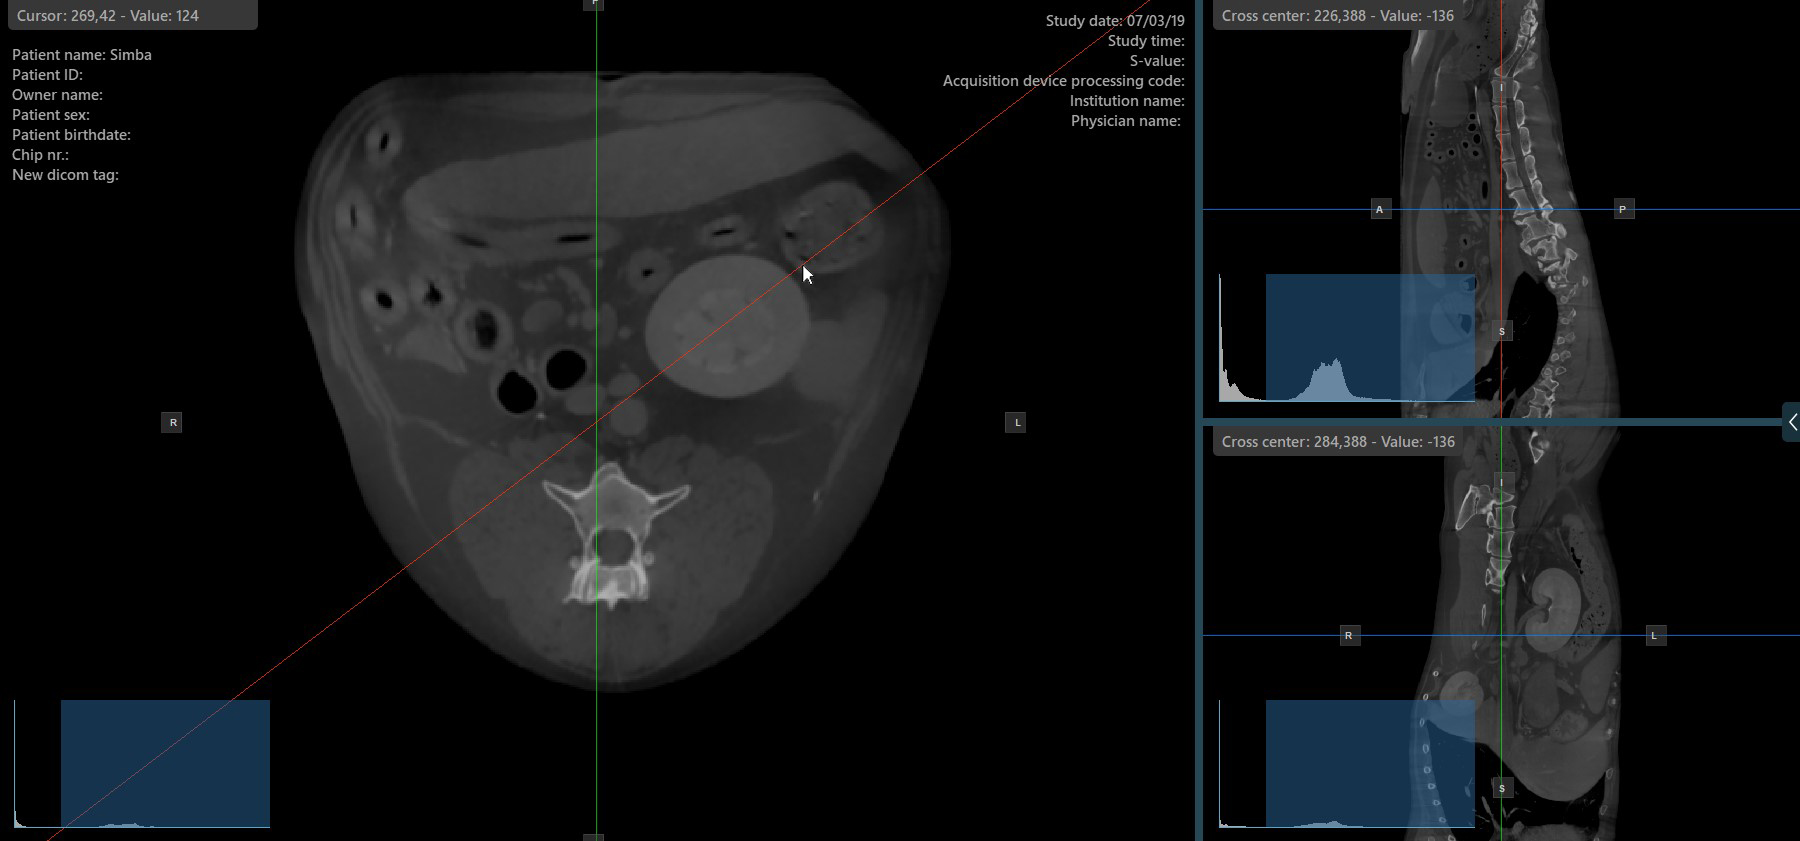

Change Slicers Cross Center Position

Altering the position of the cross center of slicers will change the position of the corresponding two image planes. The cross center of the slicers can be selected by using the Select Item (Default) tool, assigned to the right mouse button by default.

Once selected, drag the cross center of the specific slicers to the desired direction to move its position. The corresponding image planes’ orientation changes accordingly.